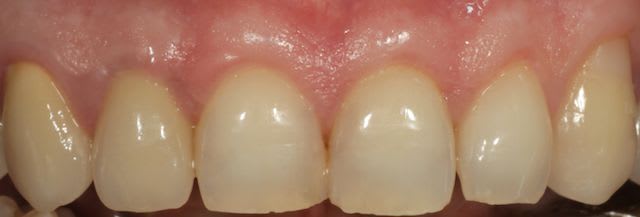

Puisqu'on parle un peu de muco, je vous propose un cas de lambeau positionné coronairement modifié selon la technique dite de Zucchelli.

à 6 semaines.

En tout cas, le résultat est splendide.

Sensibilités.

Sûr à 100% tu le seras jamais, mais dans un cas comme ça le résultat est predictible et un recouvrement à 100% peut être esperé.